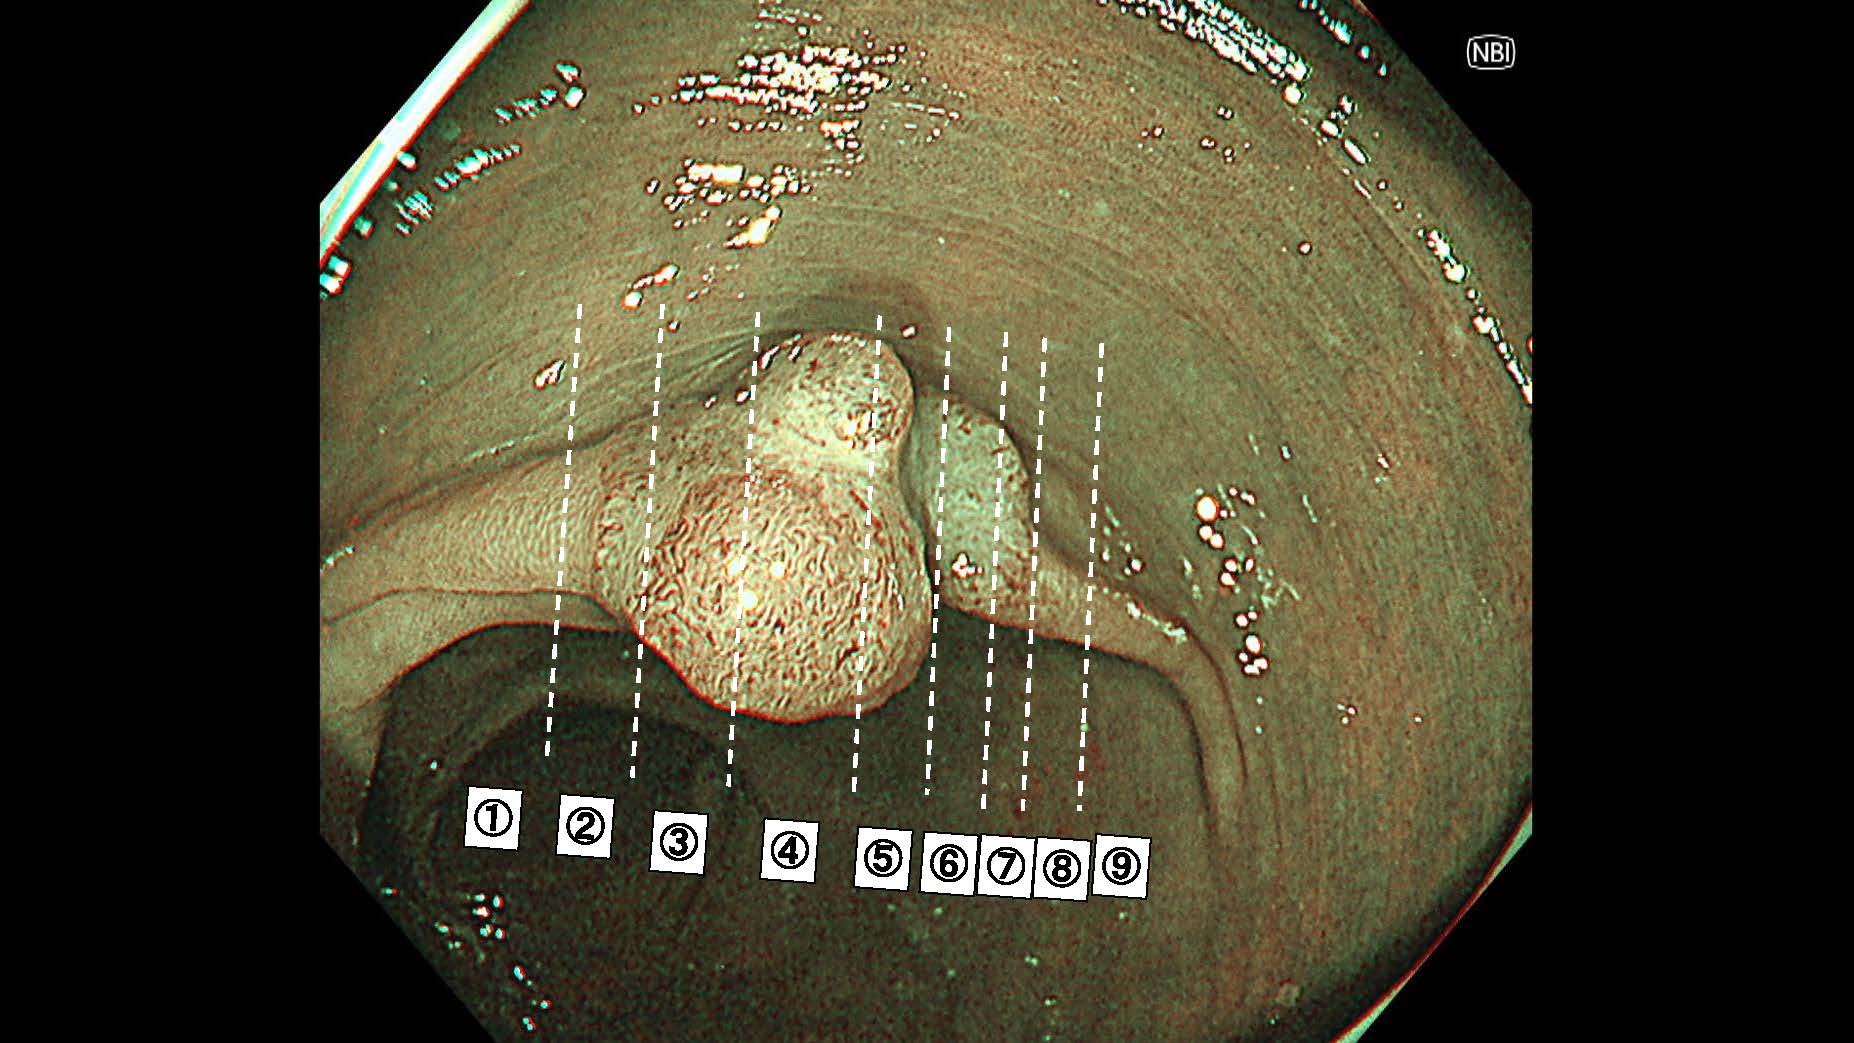

消化管Mapping~大腸~ 2025.6.11

消化管Mapping

消化管Mapping~大腸~

消化器内科

内視鏡検査・治療